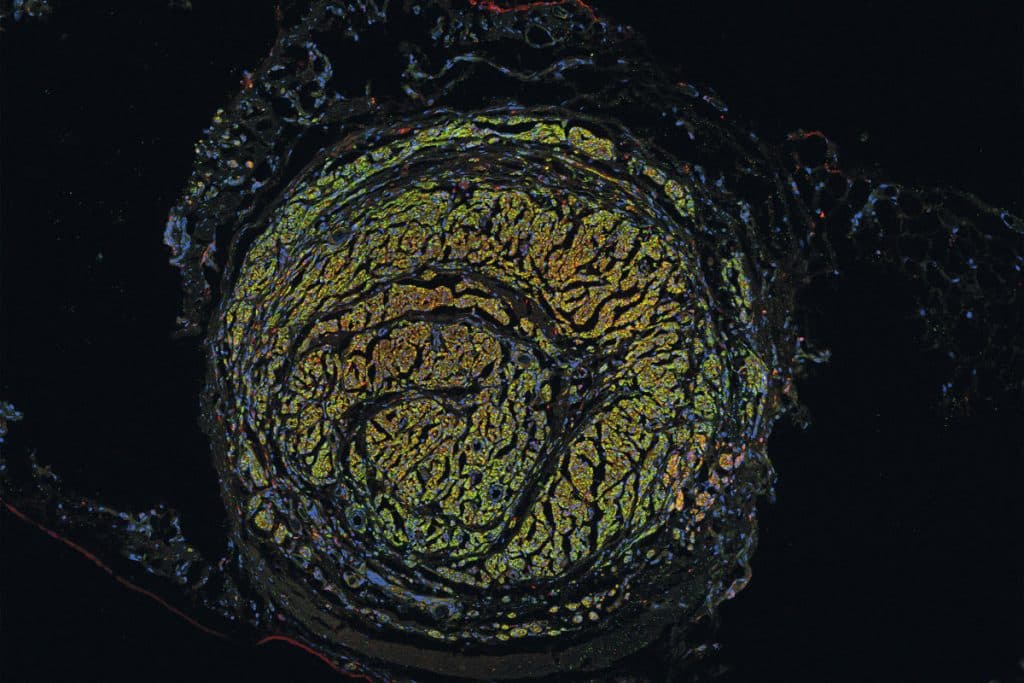

Coupe transversale d’un tube nerveux 22 semaines après une greffe de nerf sciatique chez un rat.

Dans son laboratoire rattaché au Centre de recherche en organogenèse expérimentale de l’Université Laval, situé à l’Hôpital de l’Enfant-Jésus, à Québec, François Berthod travaille d’arrache-pied à développer une meilleure solution. « Nous avons mis au point un tube vivant et prévascularisé afin de faciliter la régénérescence des fibres nerveuses. On le conçoit à partir des propres cellules du patient », indique le professeur au Département de chirurgie. Un tunnel-guide de croissance pour les nerfs, en quelque sorte. Et ça fonctionne ! Sur des souris, du moins. La découverte a été publiée en janvier 2022 dans les pages de